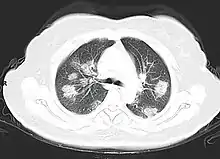

Imaging

Chest CT scans may be helpful to diagnose COVID‑19 in individuals with a high clinical suspicion of infection but are not recommended for routine screening.[167][179] Bilateral multilobar ground-glass opacities with a peripheral, asymmetric, and posterior distribution are common in early infection.[167][180] Subpleural dominance, crazy paving (lobular septal thickening with variable alveolar filling), and consolidation may appear as the disease progresses.[167][181] Characteristic imaging features on chest radiographs and computed tomography (CT) of people who are symptomatic include asymmetric peripheral ground-glass opacities without pleural effusions.[182]

Many groups have created COVID‑19 datasets that include imagery such as the Italian Radiological Society which has compiled an international online database of imaging findings for confirmed cases.[183] Due to overlap with other infections such as adenovirus, imaging without confirmation by rRT-PCR is of limited specificity in identifying COVID‑19.[182] A large study in China compared chest CT results to PCR and demonstrated that though imaging is less specific for the infection, it is faster and more sensitive.[166]